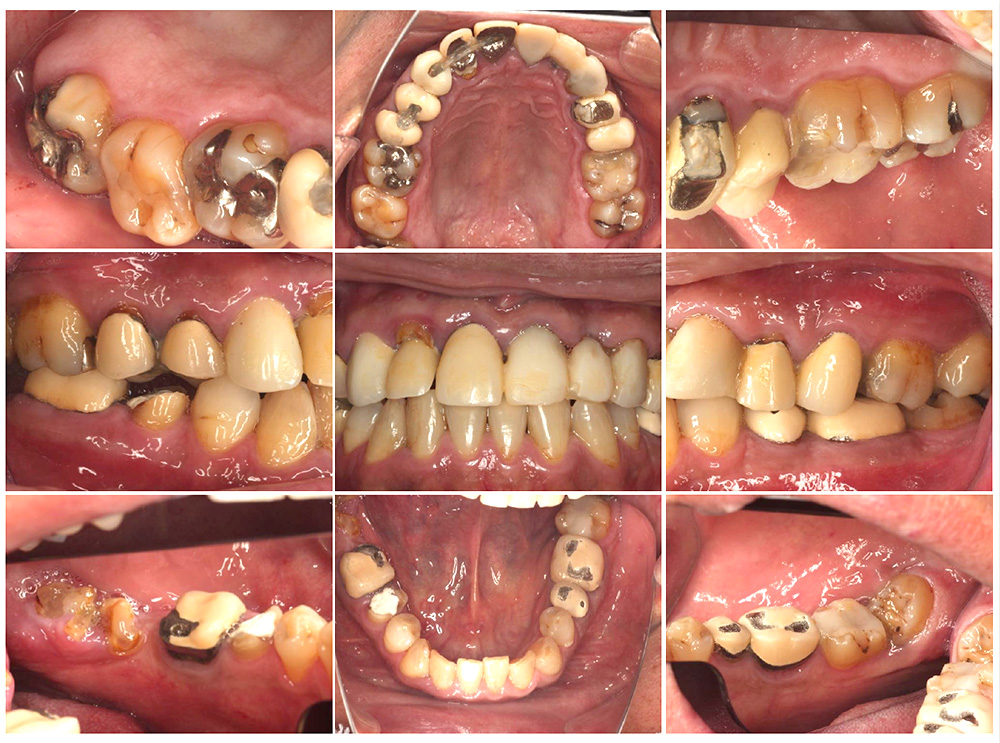

症例紹介